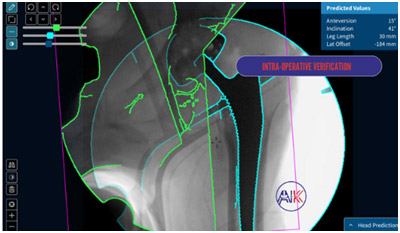

Several tailored approaches to hip replacement surgery are available to meet your specific needs. Personalised Total Hip Replacement Surgery customises the procedure to your unique anatomy and lifestyle and in cases where a previous hip replacement has failed or worn out, Revision Hip Replacement (Arthroplasty) may be necessary. This complex procedure involves removing and replacing the old prosthesis with new components, addressing any issues that have arisen since the original surgery. Revision surgery requires careful planning and advanced surgical expertise to effectively restore function and relieve pain.